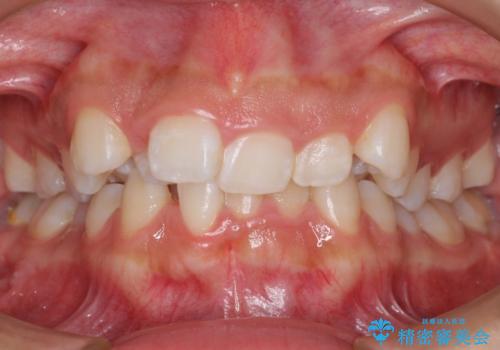

前歯のがたがた 前歯が内側に傾いている

- 前歯のがたがたを主訴に来院。

上の歯並びが前にずれて、さらに前歯が内側に倒れて過蓋咬合を呈していました。